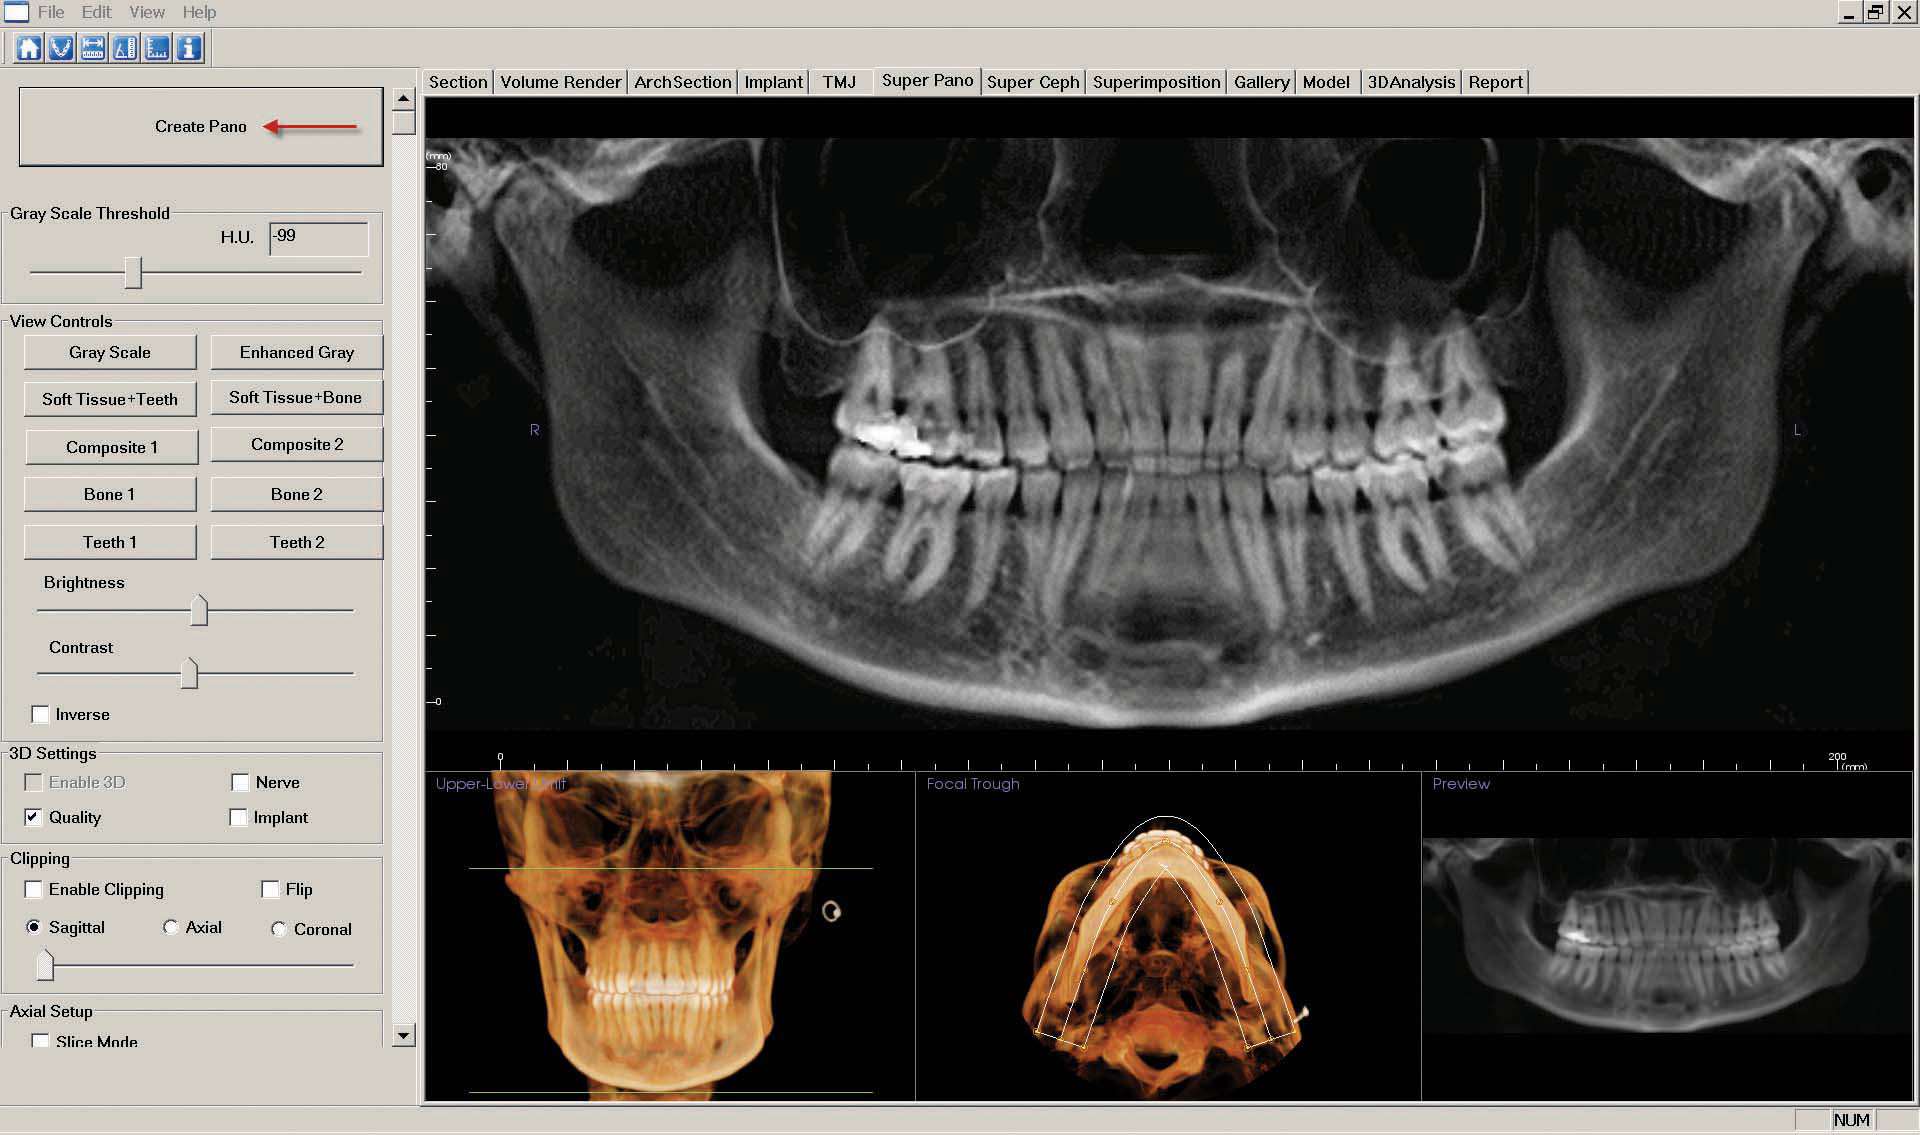

k. Select the "Super Pano" tab. Focus on the three images at the bottom. In the first image, drag the top green line to below the orbits. Then drag the bottom green line to below the chin. In the second image, adjust the white outline of the arch to frame the mandible and use the red dots to widen the arch path.

Now click the "Create Pano" button at the top left side of the screen.

As described in step 7, "Capture to Gallery" and choose the "Pano" option in the "Select Image To Capture" pop-up window. Click "OK."

Name the image "Pano" and click "OK."